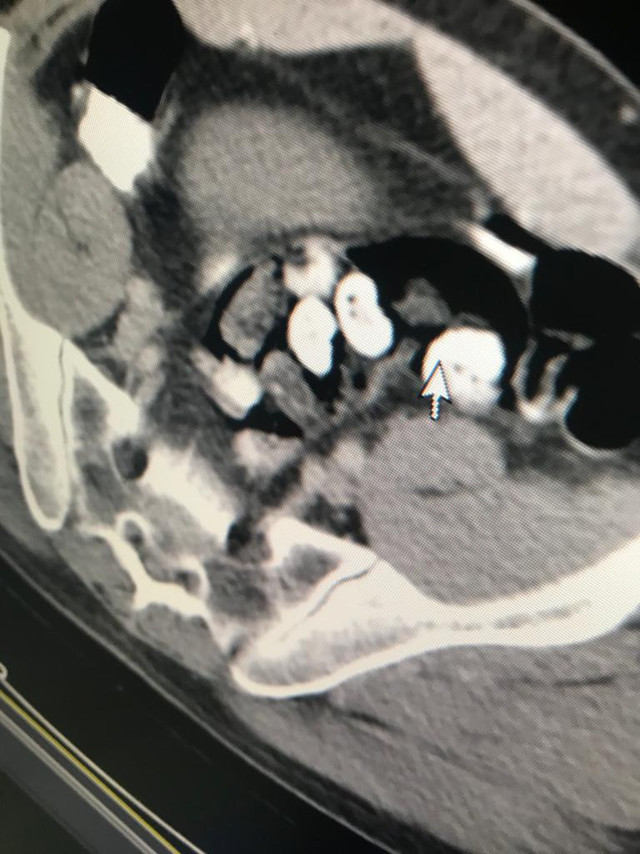

Abone olAdana İl Emniyet Müdürlüğü Narkotik Suçlarla Mücadele ekipleri, Van'dan kente uçakla gelen İranlı Faramarz T.'den şüphelendi. İlk incelemede, herhangi bir suç unsuru bulamayan polis, Faramarz T. midesinde uyuşturucu taşıyor olabileceğinden kuşkulandı. Hastaneye götürülen Faramarz T.'nin röntgen filmi çekildi.

Şüphelinin bağırsaklarında, 4 paket metanfetamin, 21 paket eroin, 22 paket afyon sakızı olduğu saptandı. Faramarz T.'nin bağırsak ve midesindeki uyuşturucular endoskopi ile çıkarıldı.